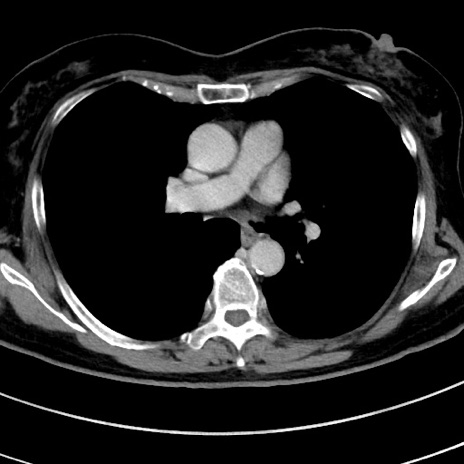

症例9(横断像)

【症例】 60歳代女性

【主訴】むかつき、みぞおちの痛み

【現病歴】3日前よりむかつきがあり、食事がとれない。

【既往歴】糖尿病

【身体所見】発熱なし、心窩部圧痛軽度あるも、腹膜刺激症状なし。

【データ】WBC 7400、CRP 1.92